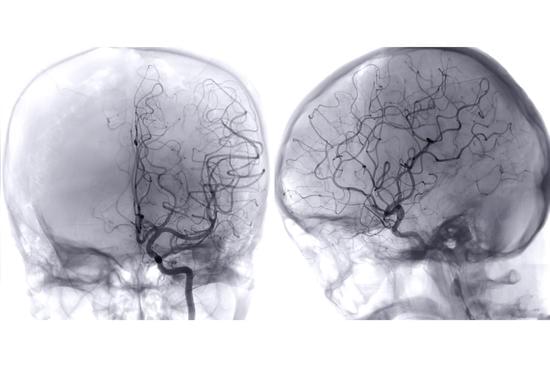

뇌혈관 조영술:

조영제를 사용하여 뇌의 혈관 상태를 시각적으로 확인합니다.